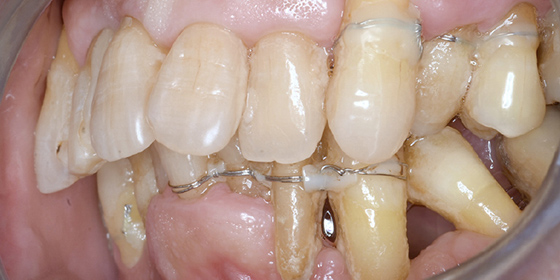

治療前

この症例では下顎の歯周病が特に進行していて、歯がクラグラで噛みにくい為、下の歯を抜歯してオールオン4で治療、上は特に歯周病が進行している左側の大臼歯を抜歯して経過観察することにしました。